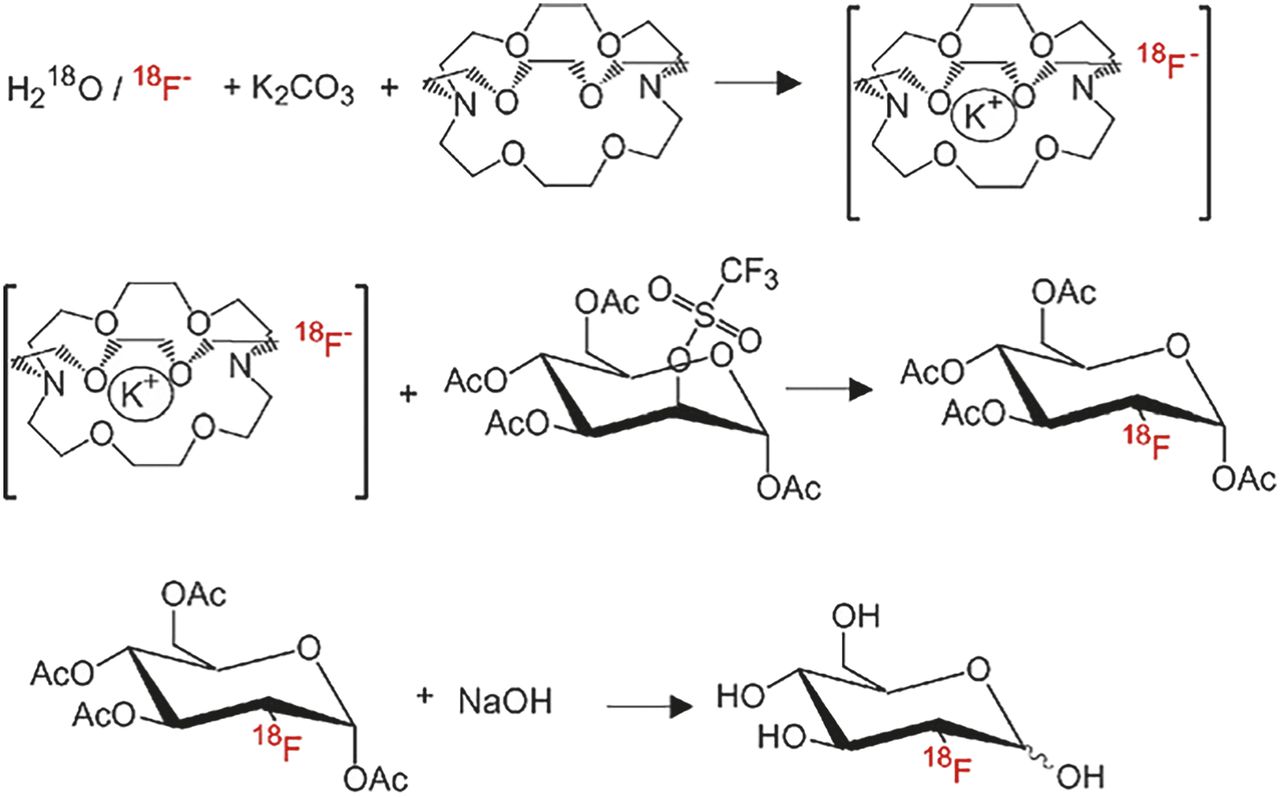

Ernst Schering Foundation Symposium Proceedings: Pet。PET Chemistry The Driving Force in Mole… PDF) PET Chemistry。PDF] Molecular Driving Forces by Ken Dill, 2nd edition。ご覧いただきありがとうございます。Advances in [18F]Trifluoromethylation Chemistry for PET Imaging。購入後、積読状態で全く読んでいません。進研ゼミ高校講座 高1 2022年度 約50冊。よろしくお願いいたします。能開センター 小6 4科目 中学受験実力判定模試。円安の今、海外より購入すると送料込みでご負担が大きいかと存じます。トイレット・トレーニングの短期集中指導法。ご検討よろしくお願いいたします。貴重⭐️中1 Z会アドバンスト模試★おまけ!さらに2年分!。

![Advances in [18F]Trifluoromethylation Chemistry for PET Imaging Advances in [18F]Trifluoromethylation Chemistry for PET Imaging](https://www.mdpi.com/molecules/molecules-26-06478/article_deploy/html/images/molecules-26-06478-g007-550.jpg)